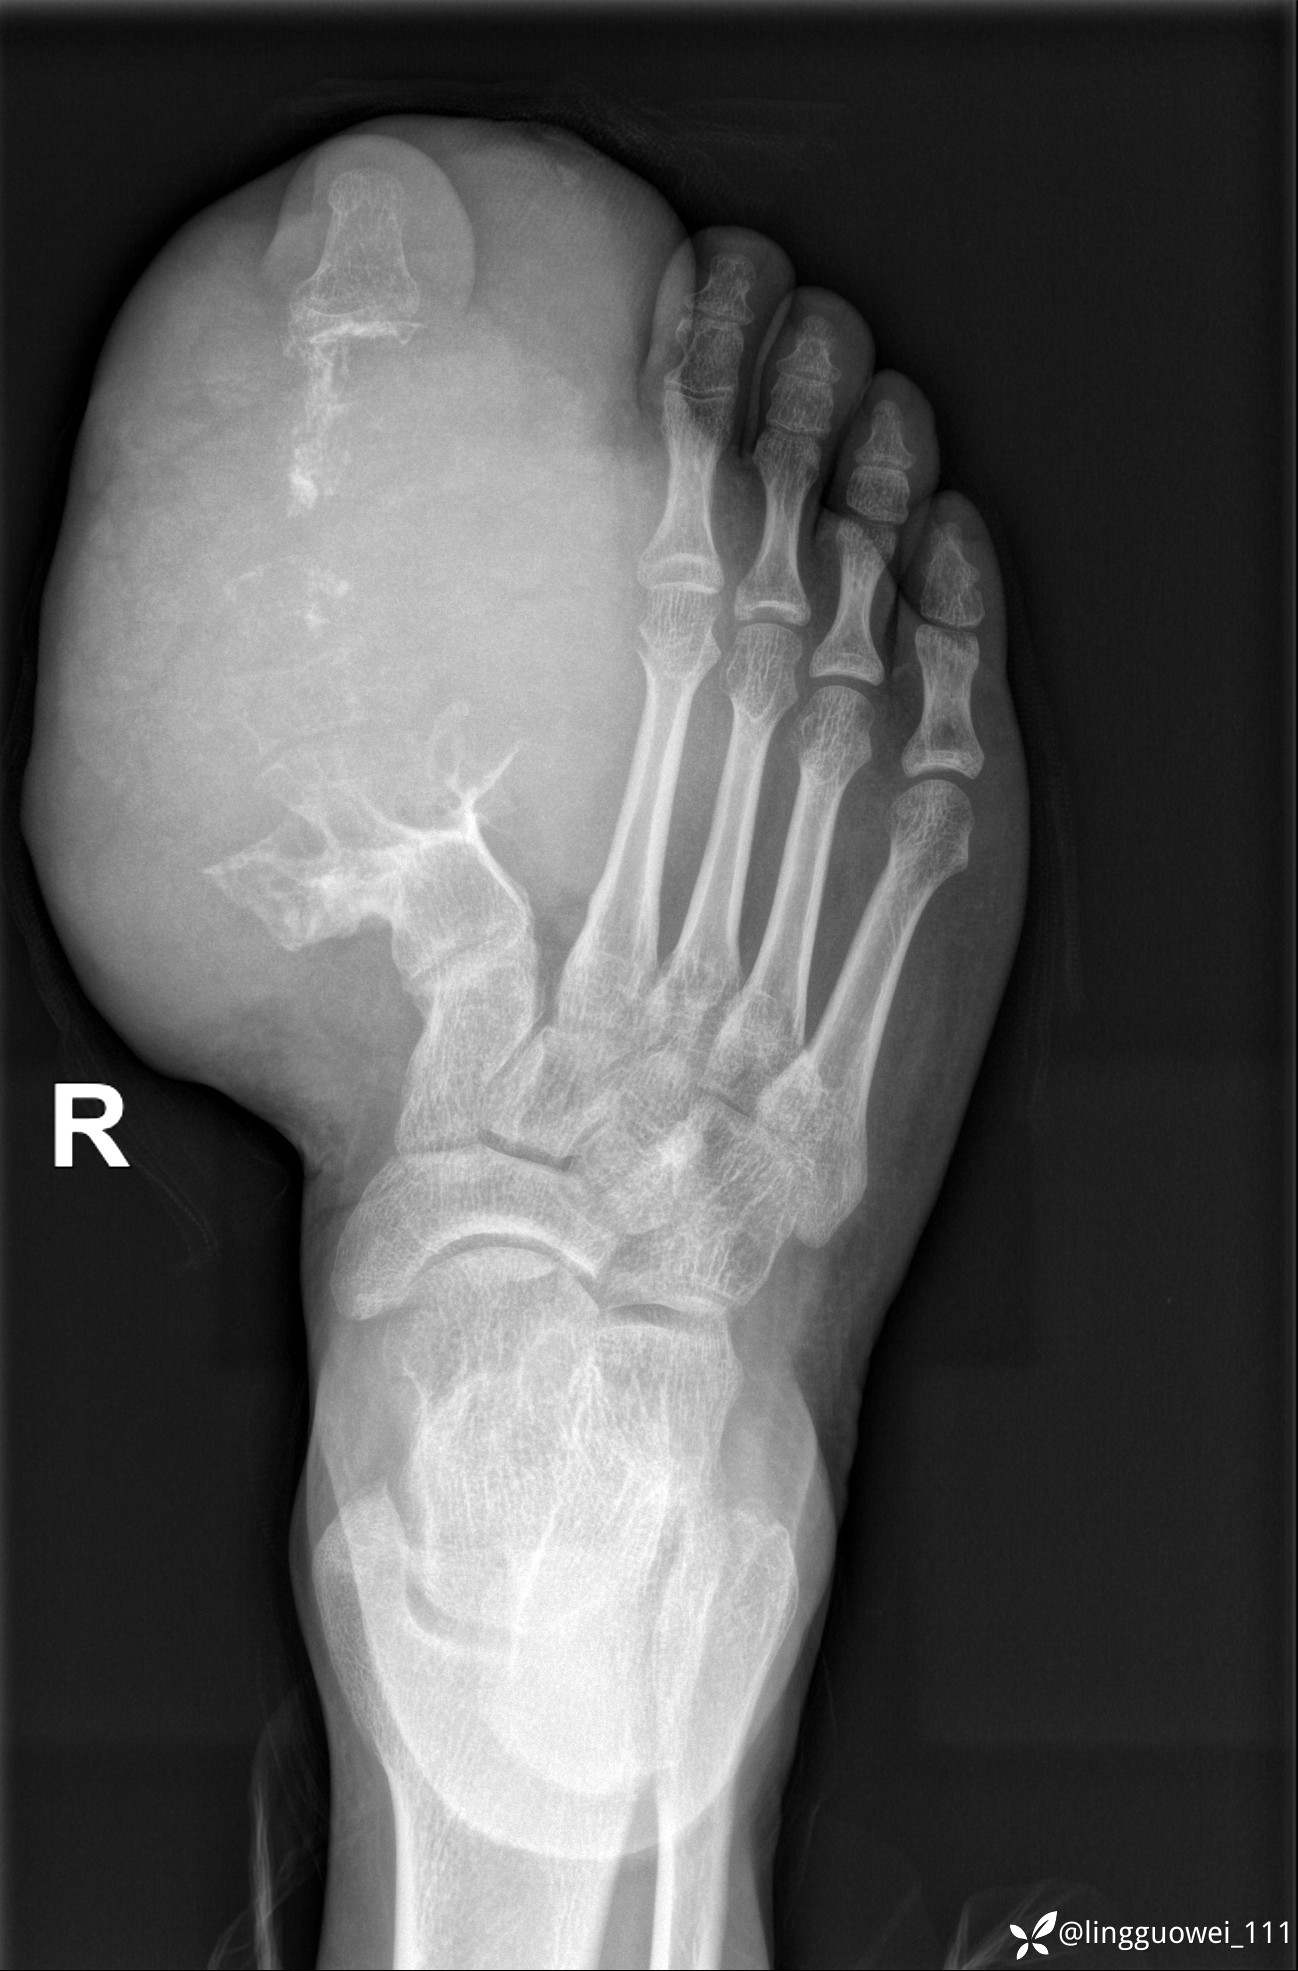

28岁男性,工作中遇到的足部最大的肿块,已补充临床资料。

28岁男性,足部肿块逐渐增大2年。能找到病因吗?

患者于2年余前高嘌呤饮食及大量饮酒后出现全身多处关节痛风石,以右足第一跖趾关节和右手为显,局部红肿热痛反复发作,自行口服药物后可缓解(药物可疑为强的松、双氯芬酸钠等,具体不详)。2年来右足痛风石明显增大,约10cm*5cm*15cm,局部红肿发热,3天前患者再次大量饮酒后痛风石顶部破溃,可见4cm*3cm皮损,较多白色豆渣样分泌物流出,为求进一步治疗来诊,门诊诊断为“右足痛风石破溃伴感染”, 收住院拟手术治疗,患者起病以来,无发热,精神佳、胃纳好、睡眠佳,大小便正常。

专科检查:右足外观畸形,足背部可见巨大痛风石形成,痛风石大小约10cm*5cm*15cm,局部皮肤红肿发热,痛风石顶部破溃,可见4cm*3cm皮损及白色豆渣样分泌物流出;痛风石界限清,质偏硬,局部触及波动感,无压痛,移动度差。右足踇趾及第2趾被痛风石压迫,关节活动受限。肢端血运、感觉无异常。 右手稍肿胀,2-5指背侧可见多发痛风石形成,最大者约花生米大小,皮肤完整未破溃,痛风石界限清,质偏硬,局部触及波动感,无压痛,移动度差。